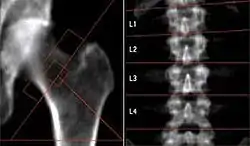

In addition to working through the risks, there will be separate investigations of NASA databases. For example, "How Long Does It Take to Rebuild Bone Lost During Space Flight?" from url=http://www.nasa.gov/mission_pages/station/research/subregional_bone.html.

The image on the right shows the loss of bone mass apparently due to long-term microgravity on the International Space Station. "[A]stronauts, on average, lost roughly 11 percent of their total hip bone mass over the course of their mission." from this report.

"The success of human exploration missions depends on finding countermeasures to overcome such effects on crew members. There are important synergies between osteoporosis research on Earth, and studies of bone loss and recovery in healthy astronauts in space. Each area of study complements the other." by Julie Robinson, International Space Station program scientist at NASA's Johnson Space Center in Houston, from the same report.